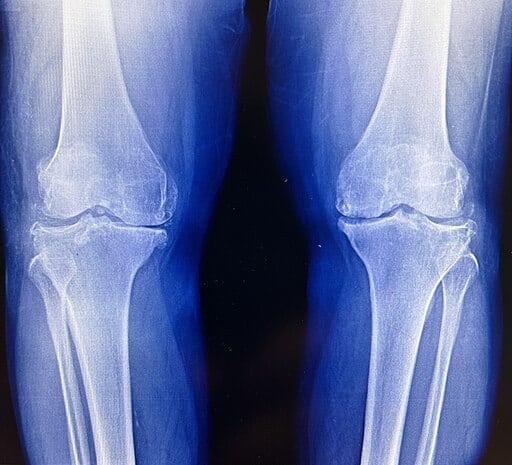

Cum se stabilește diagnosticul?

Diagnosticul începe cu consultația ortopedică și examinarea clinică a genunchiului.

Pentru confirmare, pot fi recomandate:

- Radiografia genunchiului – investigația principală

- RMN-ul – pentru evaluarea detaliată a cartilajului și a leziunilor asociate

- CT-ul – în situații speciale